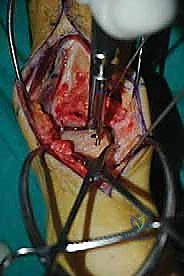

الغوص العميق في جراحة الطعم الخيفي الهيكلي (Structural Allograft Reconstruction)

يهدف هذا الإجراء العبقري إلى استبدال الغضروف والعظم التالفين والميتين بنسيج سليم تماماً مأخوذ من متبرع متوفى (طعم خيفي - Allograft). هذا الطعم يتم تعقيمه وحفظه في بنوك الأنسجة العالمية وفقاً لأعلى المعايير الطبية الصارمة لضمان خلوه من أي أمراض معدية والحفاظ على حيوية الخلايا الغضروفية.

- الترميم التشريحي الحقيقي: يسمح باستعادة الشكل الهندسي الدقيق لعظم الكاحل، بما في ذلك المنحنيات المعقدة لكتف التالوس.

- توفير غضروف طبيعي (Hyaline Cartilage): الغضروف المزروع هو غضروف زجاجي طبيعي،